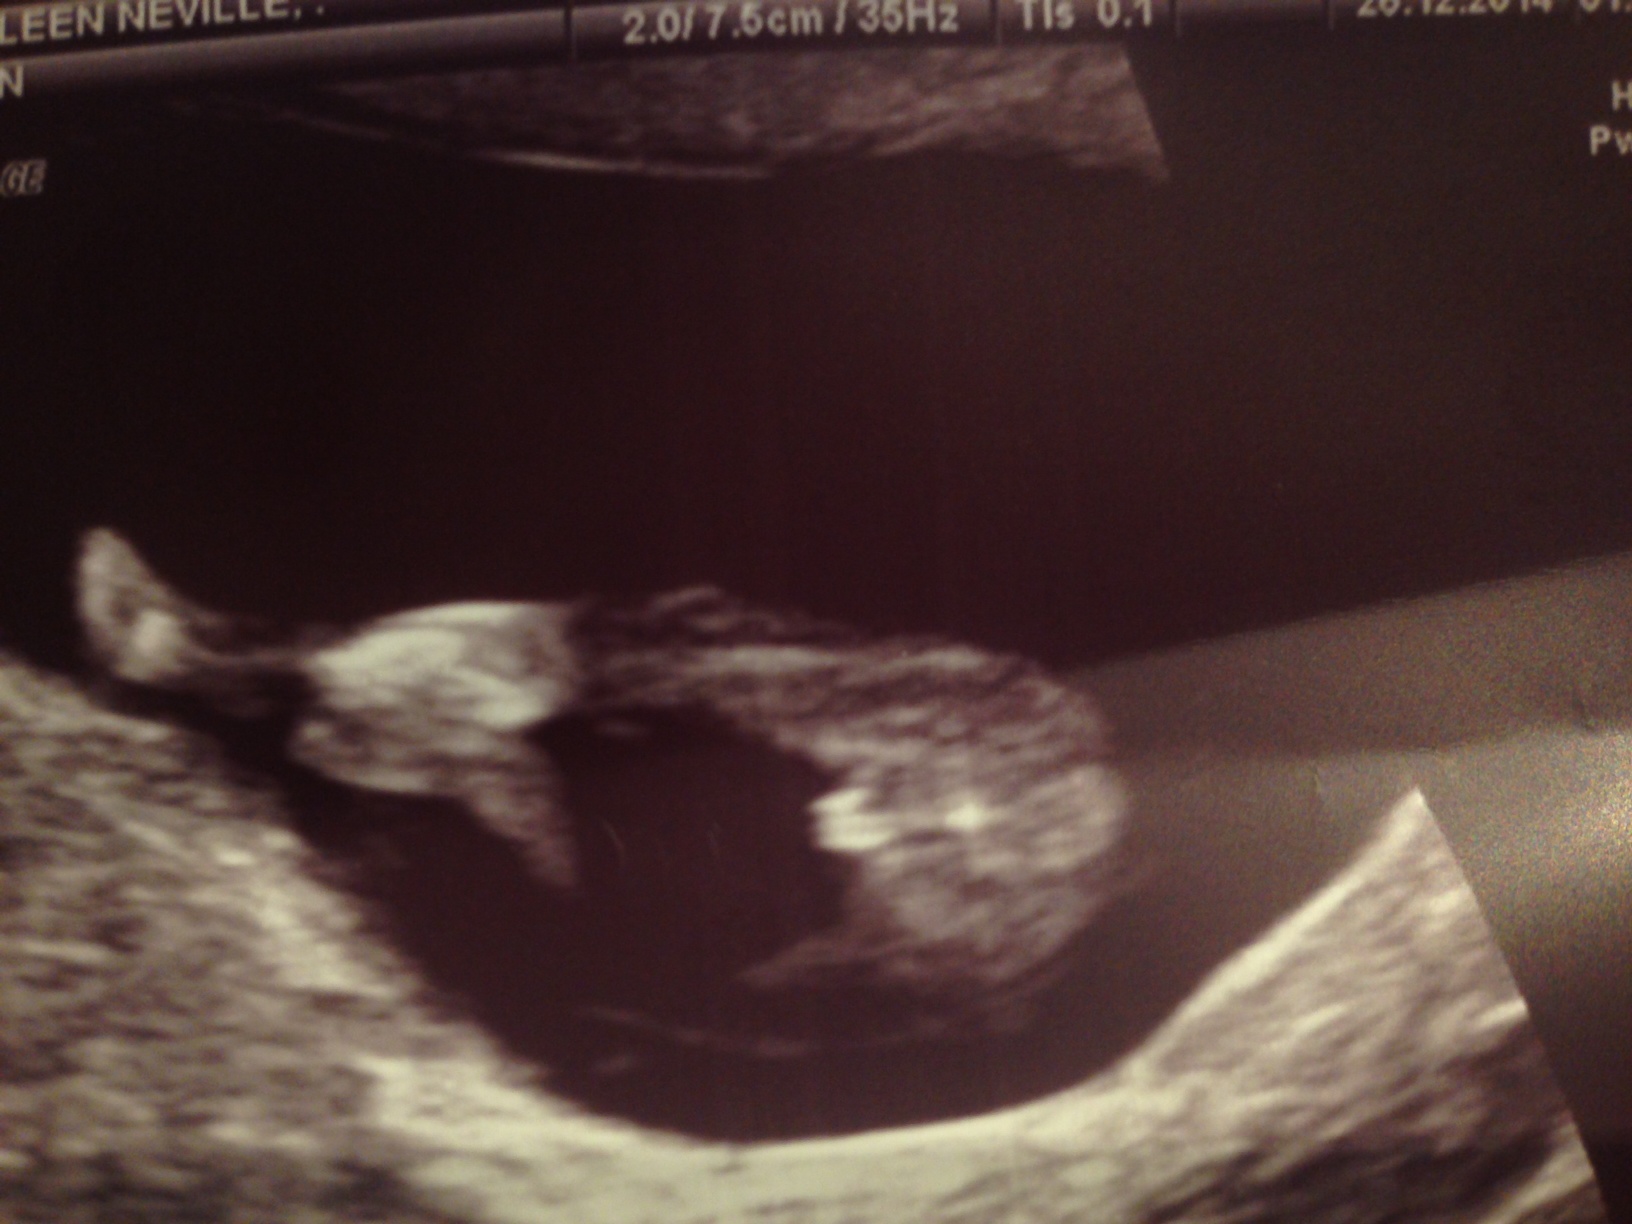

I had my 12 week scan today and my baby was measuring 12weeks 2 days. The tech got some good pics and said "it looks like a little girl, 60% lean" Im trying not to get my hopes up.... what do you think? Thanks :) Attachment 22726Attachment 22723Attachment 22724Attachment 22725